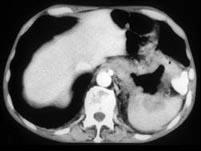

问题 男,57岁,腹部隐痛不适伴低热2月余,腋下可触及数个肿大的淋巴结,请结合图像,作出诊断 ( )

选项 A、左侧肾上腺腺瘤 B、左侧肾上腺转移瘤 C、左侧恶性嗜铬细胞瘤侵及胃脾 D、左侧肾上腺淋巴瘤且胃脾受累 E、左侧肾上腺癌并胃脾转移

答案 D